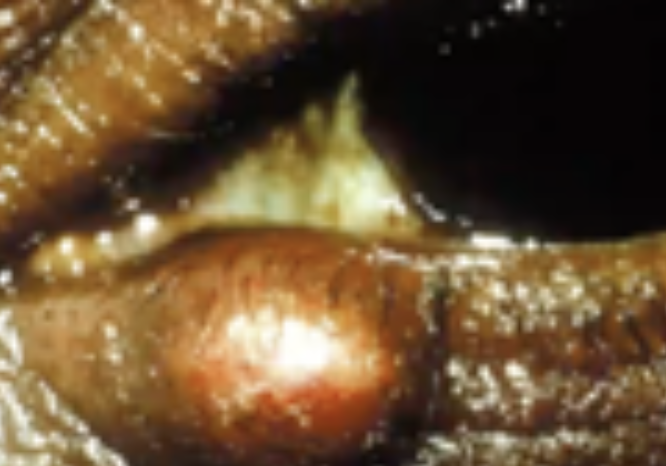

Hordeolum (Stye)

Abnormal Findings for 5. Redness, swelling, discharge, or lesions

Hair follicle infection, causes local redness, swelling, and pain

Chalazion

Abnormal Findings for 5. Redness, swelling, discharge, or lesions

Infection of the meibomian gland (located in the eyelid)

May produce extreme swelling of the lid, moderate redness, but minimal pain